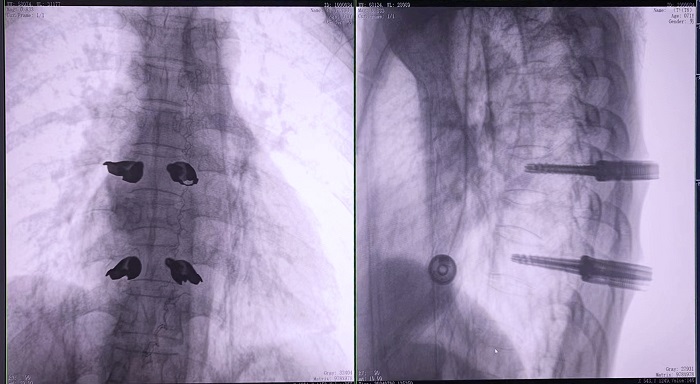

高清三維成像:普愛醫療精研三維成像技術13年,自研的三維C形臂可為手術提供清晰、穩定的三維圖像,為醫生精準開展胸椎手術提供影像保障。

亞毫米級精度:普愛醫療三維C形臂+骨科手術機器人,基于同一技術平臺研發,借助一體化自適應配準及無損圖像傳輸技術,整體協同性更高,精度可達亞毫米級。

快速掃描:麻醉師通過適當的呼吸控制,配合三維C形臂的快速掃描模式,可以在短時間內完成圖像采集,減少因呼吸運動造成的圖像干擾。